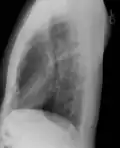

При рентгенографии грудной клетки пациент размещается между рентгеновской трубкой и плёнкой (детектором). Обычно используются прямая (передняя и задняя) и боковая (левая или правая) проекции. При исследовании в передней прямой проекции пациент помещается лицом к детектору (плёнке), при исследовании в задней прямой проекции — наоборот. При необходимости, проводятся дополнительные исследования: в положении пациента лежа на боку (для выявления гидроторакса, перемещающегося при перемене положения тела), выгнувшись назад (лордотическая рентгенограмма, для лучшей визуализации верхушек лёгких, например, при исключении опухоли Панкоста), на выдохе (для лучшей диагностики пневмоторакса), в косых проекциях.